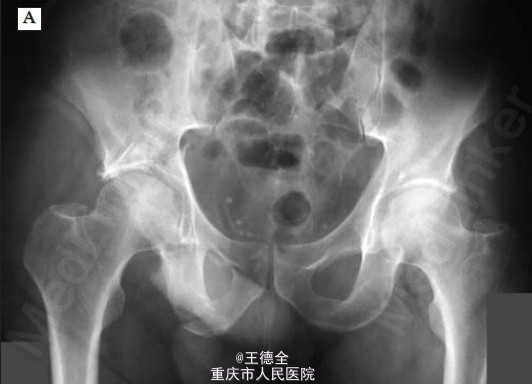

右侧髋部骨折一例

患者男性,42岁,车祸伤入院,完善检查后发现右侧髋部骨折,遂手术治疗。